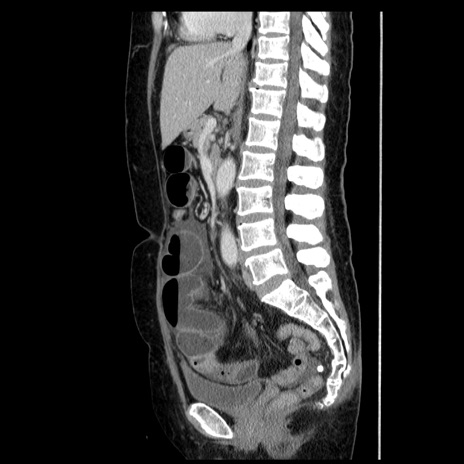

症例6(矢状断像)

【症例】50歳代女性

【主訴】下腹部痛

【現病歴】本日朝より下痢2回あり。 昼食を食べた後、嘔吐3回、下腹部痛認め、症状軽快せず、当院救急搬送。

最終食事:本日昼(生ものなし)。 昨日の夜、刺身を食ぺたとのこと。周囲に同様の症状の者なし。普段、排便は毎日あるとのこと。

【既往歴】卵巣癌術後(8年前に当院で卵巣摘出)

【身体所見】 意識清明、腹部:平坦、腸蠕動音→、やや硬、下腹部自発痛・圧痛あり、反跳痛あり、筋性防御なし。

【データ】WBC 16000、CRP 0.01